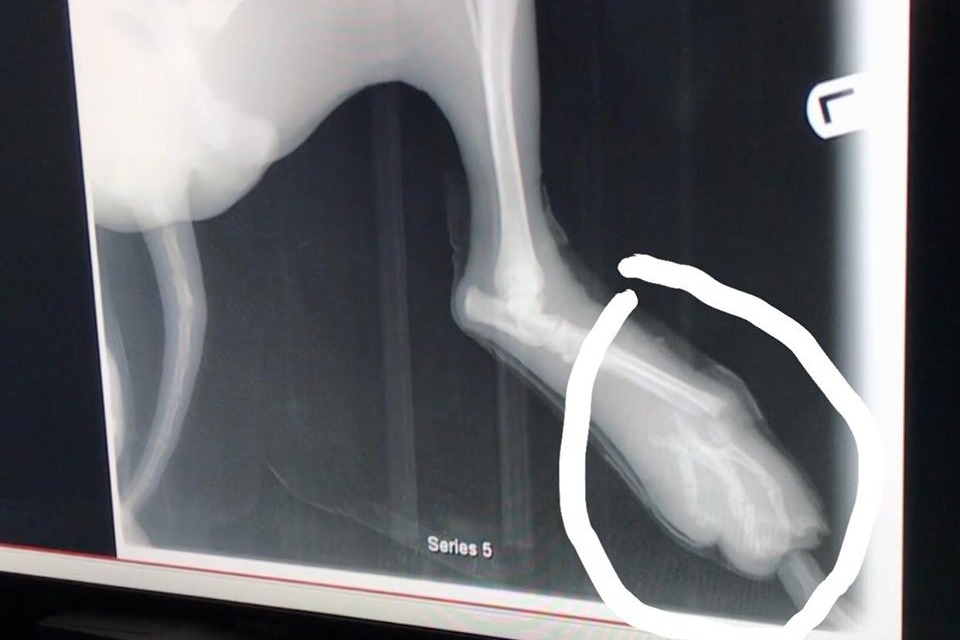

The dog was hit by a car and sustained some serious injuries to her legs. The young lady’s name is Sarai. She named the dog Merida. Sarai took Merida to the vet in San Felipe, but after they told her that they will have to amputate both Merida’s legs, she drove all the way to Mexicali to see another vet. The vet in Mexicali said that Merida will need three surgeries, and they are certain they can save her legs.